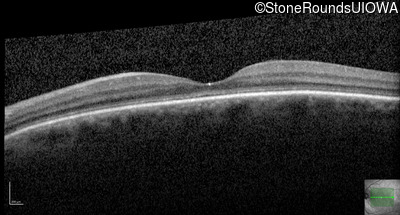

Age at visit:

66 years

OD

OS

10/125

OCT Stack